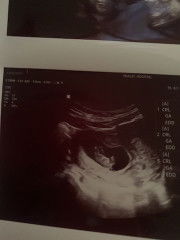

ท้อง 22 สัปดาห์ ทารกในครรภ์ ขาสั้นกว่าเกณฑ์ 1 เดือน

#ขอคำแนะคำปรึกษาคะ แม่ๆท่านไหนเคยเจอหรือมีประสบการณ์ ทารกในครรภ์ ขาสั้นกว่าเกณฑ์ 1 เดือน คลอดน้องออกมาน้องขาปกติมั้ยค่ะ